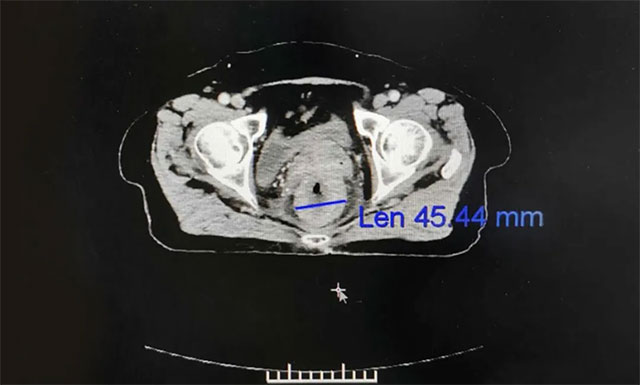

隨后,劉女士在醫(yī)院進行一個療程的放療治療,放療期間未見明顯不良反應(yīng),恢復良好。對于這次放療效果,李女士還是很滿意的,她講道:“經(jīng)過這次放療,之前肛門處流脹、里急后重及墜脹的癥狀明顯改善,現(xiàn)在夜里終于無便意,可以一覺睡到天亮,這種感覺真是太好了,而且在醫(yī)院這一個多月我竟然還胖了3斤,現(xiàn)在心情也好了很多,特別感謝藍十字放療科的所有醫(yī)護人員們”。

▲ 放療后患者病灶縮小,病癥逐漸緩解